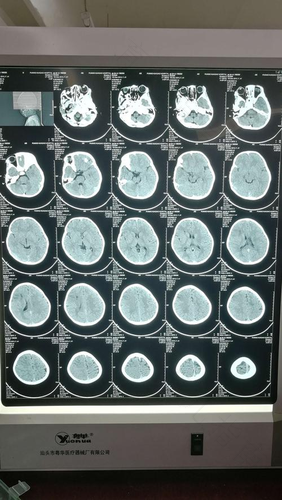

在看什么东西的时候也不是直视,而是斜着看,凝视,往上看的时候眼球会表现出很困难的症状。还会有发热,频繁哭闹,头痛,没有原因不能解释的黄疸,贫血等症状。这些都是婴儿颅内感染的初期症状。

在发现流感颅内感染初期症状的症状以后,需要通过合理的方法及时有效的治疗,稍微放松或是忽视,对于其健康都是有极大影响的。及时得不到处理,病情恶化导致严重的后果。

尤其是治疗不及时或是不彻底的话,有少部分宝宝会有失明的可能性,还有可能出现智力低下,听力慢慢退化等后遗症。所以要积极的预防治疗婴儿颅内感染,另外婴儿还要加强锻炼,增强抵抗力。